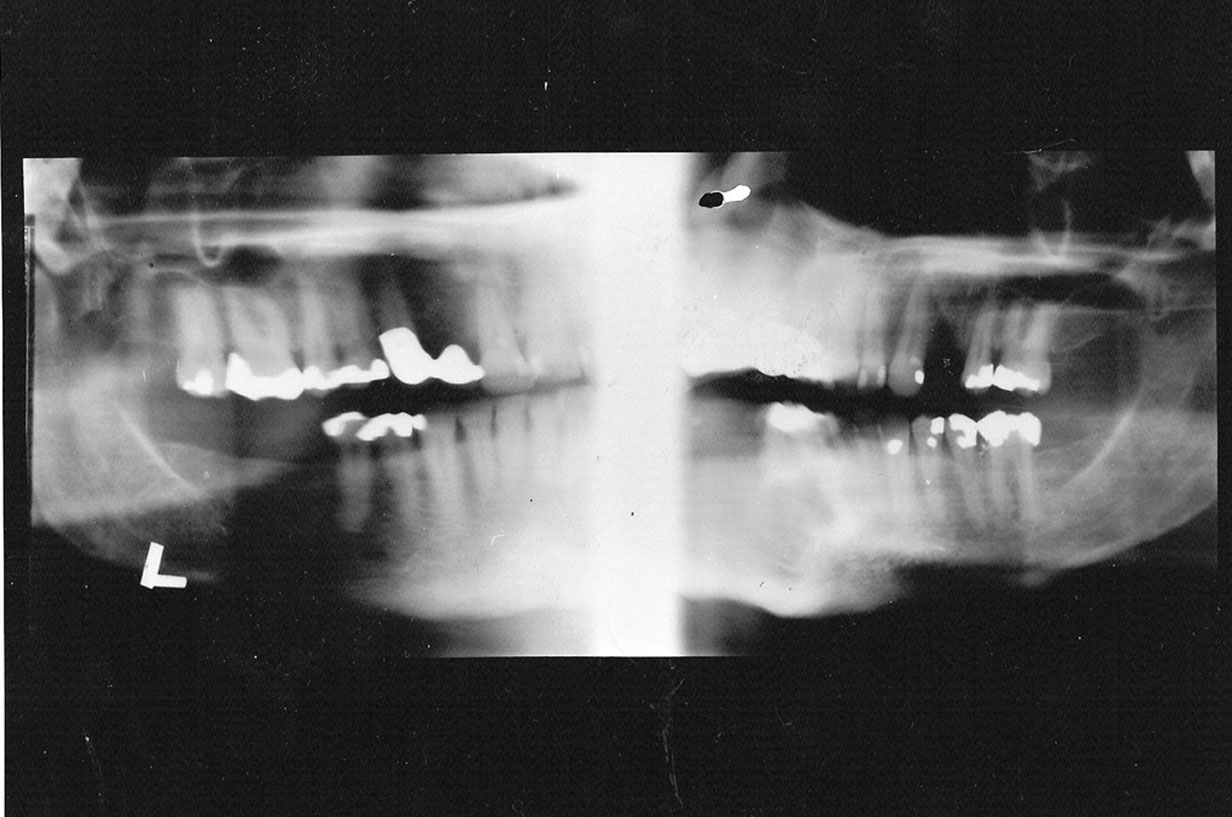

If the patient’s head is positioned too high, or if the film cassette and tubehead are too low, the superior part of the condyles of the ramus and much of the maxilla will be missing from the film, as in Figure 20. In the reverse situation, if the patient’s head is too low, or the cassette and tubehead are too high, the lower border of the mandible will be lost.

Figure 20. Vertical height.

Figure 20